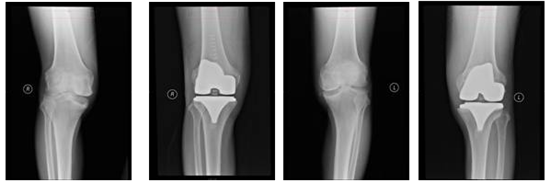

四川新闻网雅安1月8日讯(余强 文/图)2018年12月,雅安职业技术学院附属医院外二科(骨科)应用目前国内最新3D打印辅助技术,成功为3人4膝(2人单侧,1人双侧)进行个性化全膝关节置换手术,取得了良好的治疗效果。

3名患者中,有一位是来自甘孜州雅江县的精准扶贫患者。因其双膝骨性关节炎完全丧失劳动力,入院时中度贫血,按照常规手术方式,患者只能先进行单侧手术,等待三个月左右才能实施另一侧手术,期间还可能需要输血治疗。对该患者采用3D打印辅助技术,左侧全膝关节置换术1周后即实施右侧全膝关节置换术,术后患者恢复良好,关节功能迅速康复并住院4周后康复出院,住院及手术期间未输血治疗,出院时患者贫血已恢复为轻度贫血,口服铁剂补血治疗。通过对3D打印技术辅助膝关节置换的临床应用与观察,该技术的临床应用具有减少手术创伤与出血、手术恢复快、治疗时间短等优点,为患者节省大量时间及费用。

3D打印技术,是一种以数字模型文件为基础,运用粉末状金属或塑料等可粘合材料,根据不同患者的需要快速而精确地制作个性化医用材料,并能同时对材料的微观结构进行精确控制。术前通过CT扫描患者下肢,将获取的数据导入到相关软件,在电脑上对数据进行分析,确定股骨、胫骨相关参数及患肢力线后进行三维重建。然后模拟人工全膝关节置换术过程,确定股骨、胫骨的截骨平面。最后模拟化设计手术中用于截骨的导向导板,进行3D打印获得手术导板。需要强调的是,在全膝关节置换术中,手术导板的精准设计是该手术取得成功的重要保证,因此也是术前准备最为关键的一环。这一步就好比裁缝利用手中的尺子为顾客进行“量体”的过程。术中操作简化了手术步骤,只需将截骨导板贴附于关节表面,然后实施定位截骨即可,手术操作简单,准确性高于传统方法,避免了人为因素的干扰。这一步就好比裁缝为顾客进行“裁衣”的过程。每一个患者使用的都是全世界唯一的截骨导板,通过“量身订制”,术中操作精细、避免个人经验干扰、术后下肢力线精确,保证术后关节功能快速康复。

这一新技术为雅安市关节置换术的首次临床应用,填补了3D打印技术在雅安市该医疗领域的应用空白,取得了良好的社会效益。